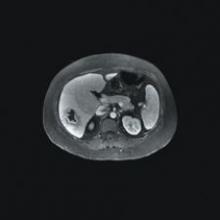

Cedara Software today announced that it will unveil several new oncology solutions, including multimodality image fusion that supports deformable registration in PET/CT software, at the American Society of Therapeutic Radiology and Oncology Conference (ASTRO), held November 5-9 in Philadelphia, Pennsylvania.